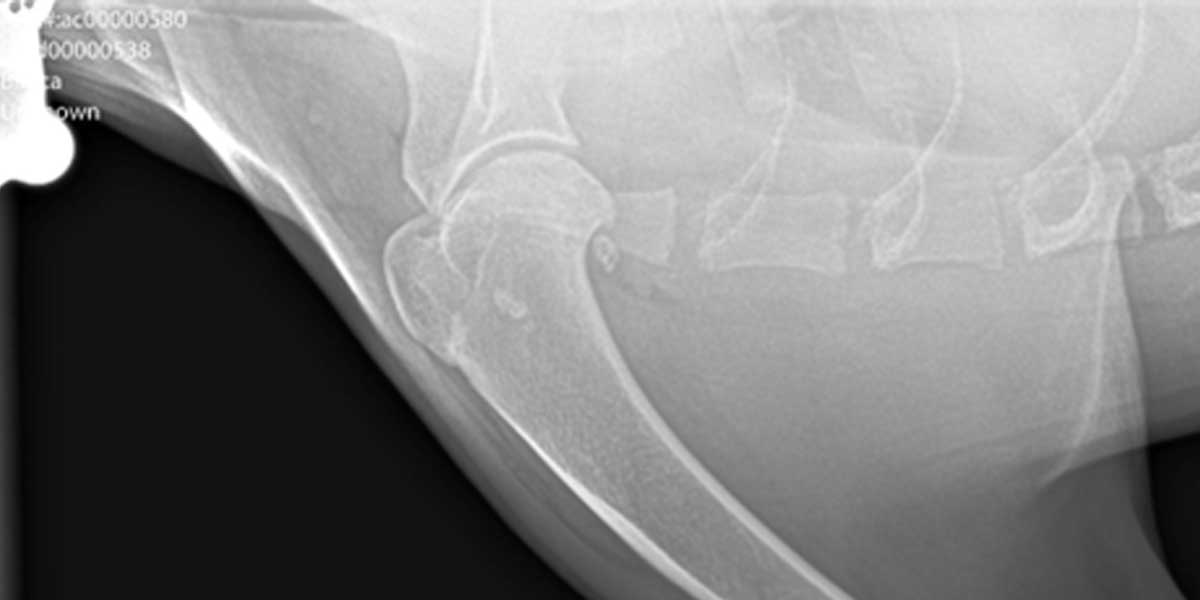

Dijagnoza se postavlja na temelju kliničkog pregleda i rendgenskih snimaka zahvaćenog zgloba. U određenim slučajevima koriste se i naprednije metode poput CT-a ili artroskopije radi preciznije procjene.